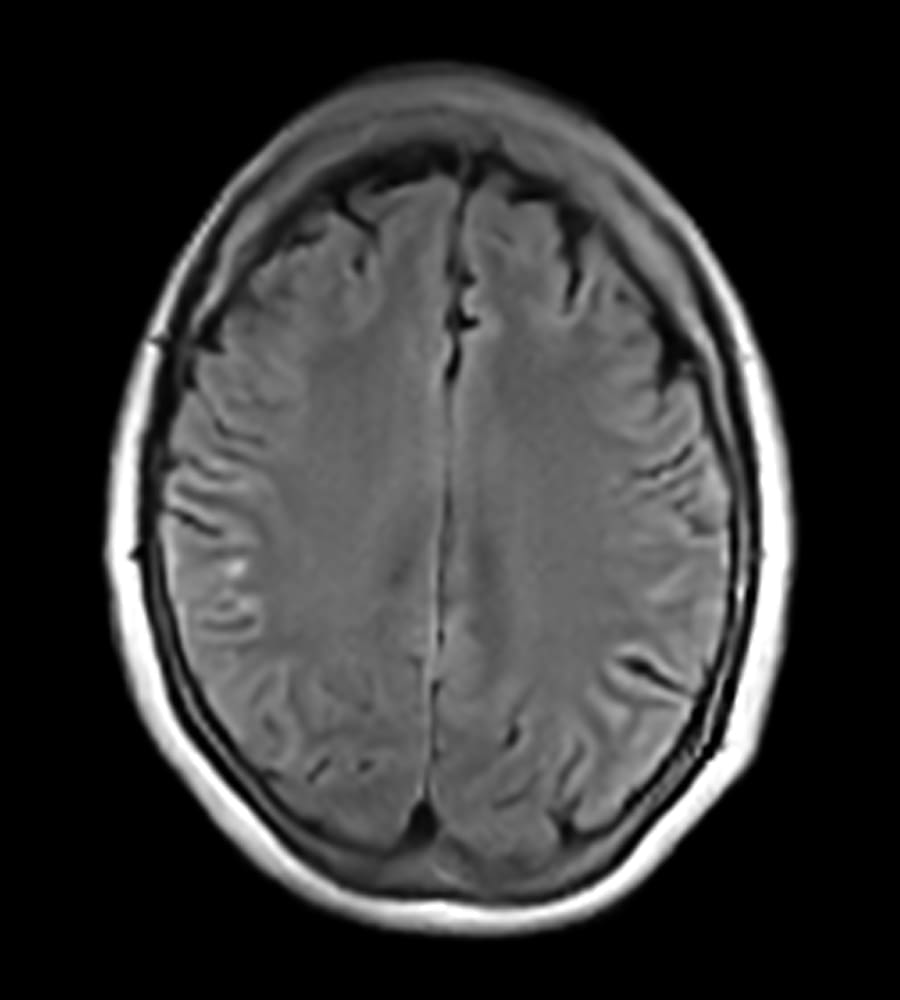

Clinical Images

Clinical case types: Headache, Migraine, Multiple Sclerosis, Micro Vascular Disease and Tumor Routine Follow-up.